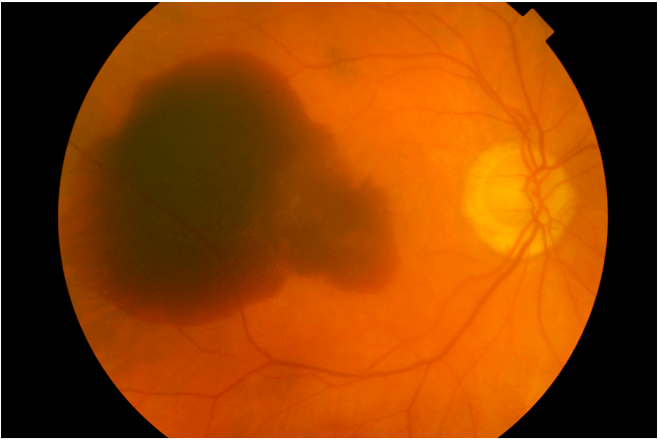

Rarely, if a patient with wet AMD develops a large bleed at the back of the eye this blood can accumulate under the macula. This is called a submacular haemorrhage (SMH) and if untreated often leads to permanent vision loss.

A SMH will eventually clear on its own - however blood is harmful when in direct contact with the macula and may cause scarring and permanent central vision loss if left too long. Thus, keys to treat SMH are to stop further bleeding and help blood clear away faster (or at least to push it away from the macula).